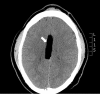

Figure 2

Brain CT—horizontal plane, white arrow shows a large, well-defined low-density lesion involving the genu and body of the corpus callosum.